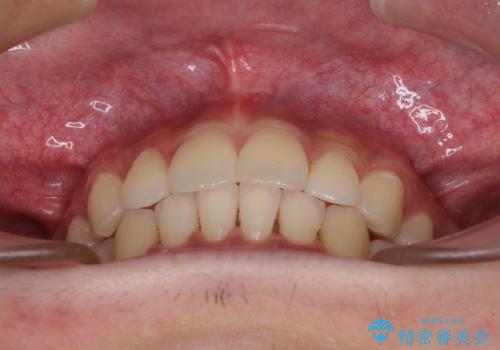

インビザライン・ライトは提供されるマウスピースの数に制限があり、通常のタイプよりもマウスピース提供期間が短くなっている一方、安価に治療を行うことができるプランです。

治療のゴールも変更できないため、軽微な歯列不正や、後戻り改善などに適しています。